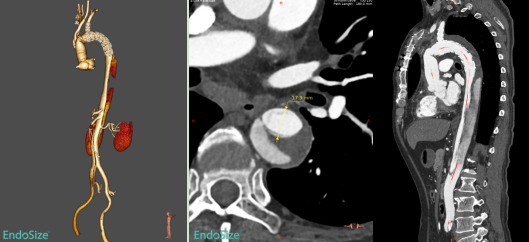

术前,胡佳主任医师团队对患者病情进行了详尽的术前评估和反复讨论,经过精细影像学分析和手术模拟推演,制定了个体化手术治疗方案。术中,患者全麻后采用左侧股动脉穿刺建立通路,主动脉造影证实象鼻支架以远残余夹层真腔狭窄,存在多发内膜破口。手术选用近端直径30mm、远端直径24mm、长度290mm的A型夹层全腔内重建系统,其中覆膜段长度为120mm。支架近端锚定于象鼻支架内,远端锚定于肾下腹主动脉。手术过程顺利流畅,术后即刻造影显示胸段残余夹层近端破口有效覆盖,近端假腔不再显影,远端真腔扩张良好,手术治疗效果达到预期。

术后复查的CTA